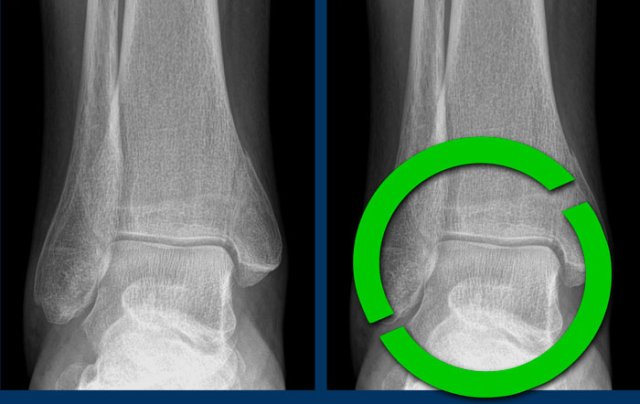

The findings are:

• vertical fracture of the medial malleolus (yellow arrow).

This is not an avulsion or pull-off fracture, but a push-off fracture.

• Maybe there is an avulsion of the lateral malleolus (white arrow), but that is not sure.

However this does not matter as we will show in a moment.

A vertical fracture of the medial malleolus is a push-off fracture.

According to Lauge-Hansen the fracture results from an adduction force on the supinated foot

The lateral side is under extreme tension with stretch on the lateral collateral band.

In stage 1 there is either a rupture of the lateral collateral band or an avulsion fracture (which we also know as Weber A).

In stage 2 there is always a vertical fracture of the medial malleolus and there has to be either an avulsion of the lateral malleolus or a rupture of the collateral band as these sequences always are in this order with first stage 1 and then stage 2.

This means, that whether we see a fracture on the lateral side or not, it doesn't matter.

There must be an injury to both the medial aswell as the lateral side and we now know that the ankle is unstable, because the ring of stability is broken in two places.

Here another unstable ankle fracture.

According to Lauge-Hansen this is SA stage 2.

According to Weber this is Weber A with additional fracture to the medial malleolus.